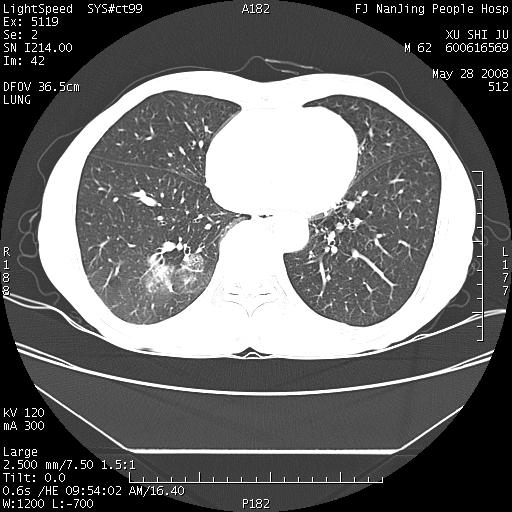

以下是引用杀毒软件在2008-5-28 19:16:00的发言:[br]病灶旁“晕轮征”,考虑肺真菌病

以下是引用qiushi在2008-5-28 20:01:00的发言:[br]空洞周围环状磨玻璃影(日晕征),考虑肺曲霉菌病.

以下是引用yuhongjun在2008-5-29 4:28:00的发言:[br]空洞周围环状磨玻璃影(日晕征),考虑肺曲霉菌病。支持! [br] [br]

以下是引用lrj在2008-5-28 21:10:00的发言:[br]所示应该是正常结构,是对称的,多个层面都有!也不像是内乳动脉或是肿大淋巴结![br]右下肺渗出性病变伴空洞形成,其洞内见一结节,以下诊断都有可能:1 右下肺曲菌感染, 2右下肺结核空洞形成伴曲菌感染!3右下肺结核空洞伴壁内占位形成,虽说后者发生的几率很低 但作为我们应该多考虑一下吧!最重要的结合临床